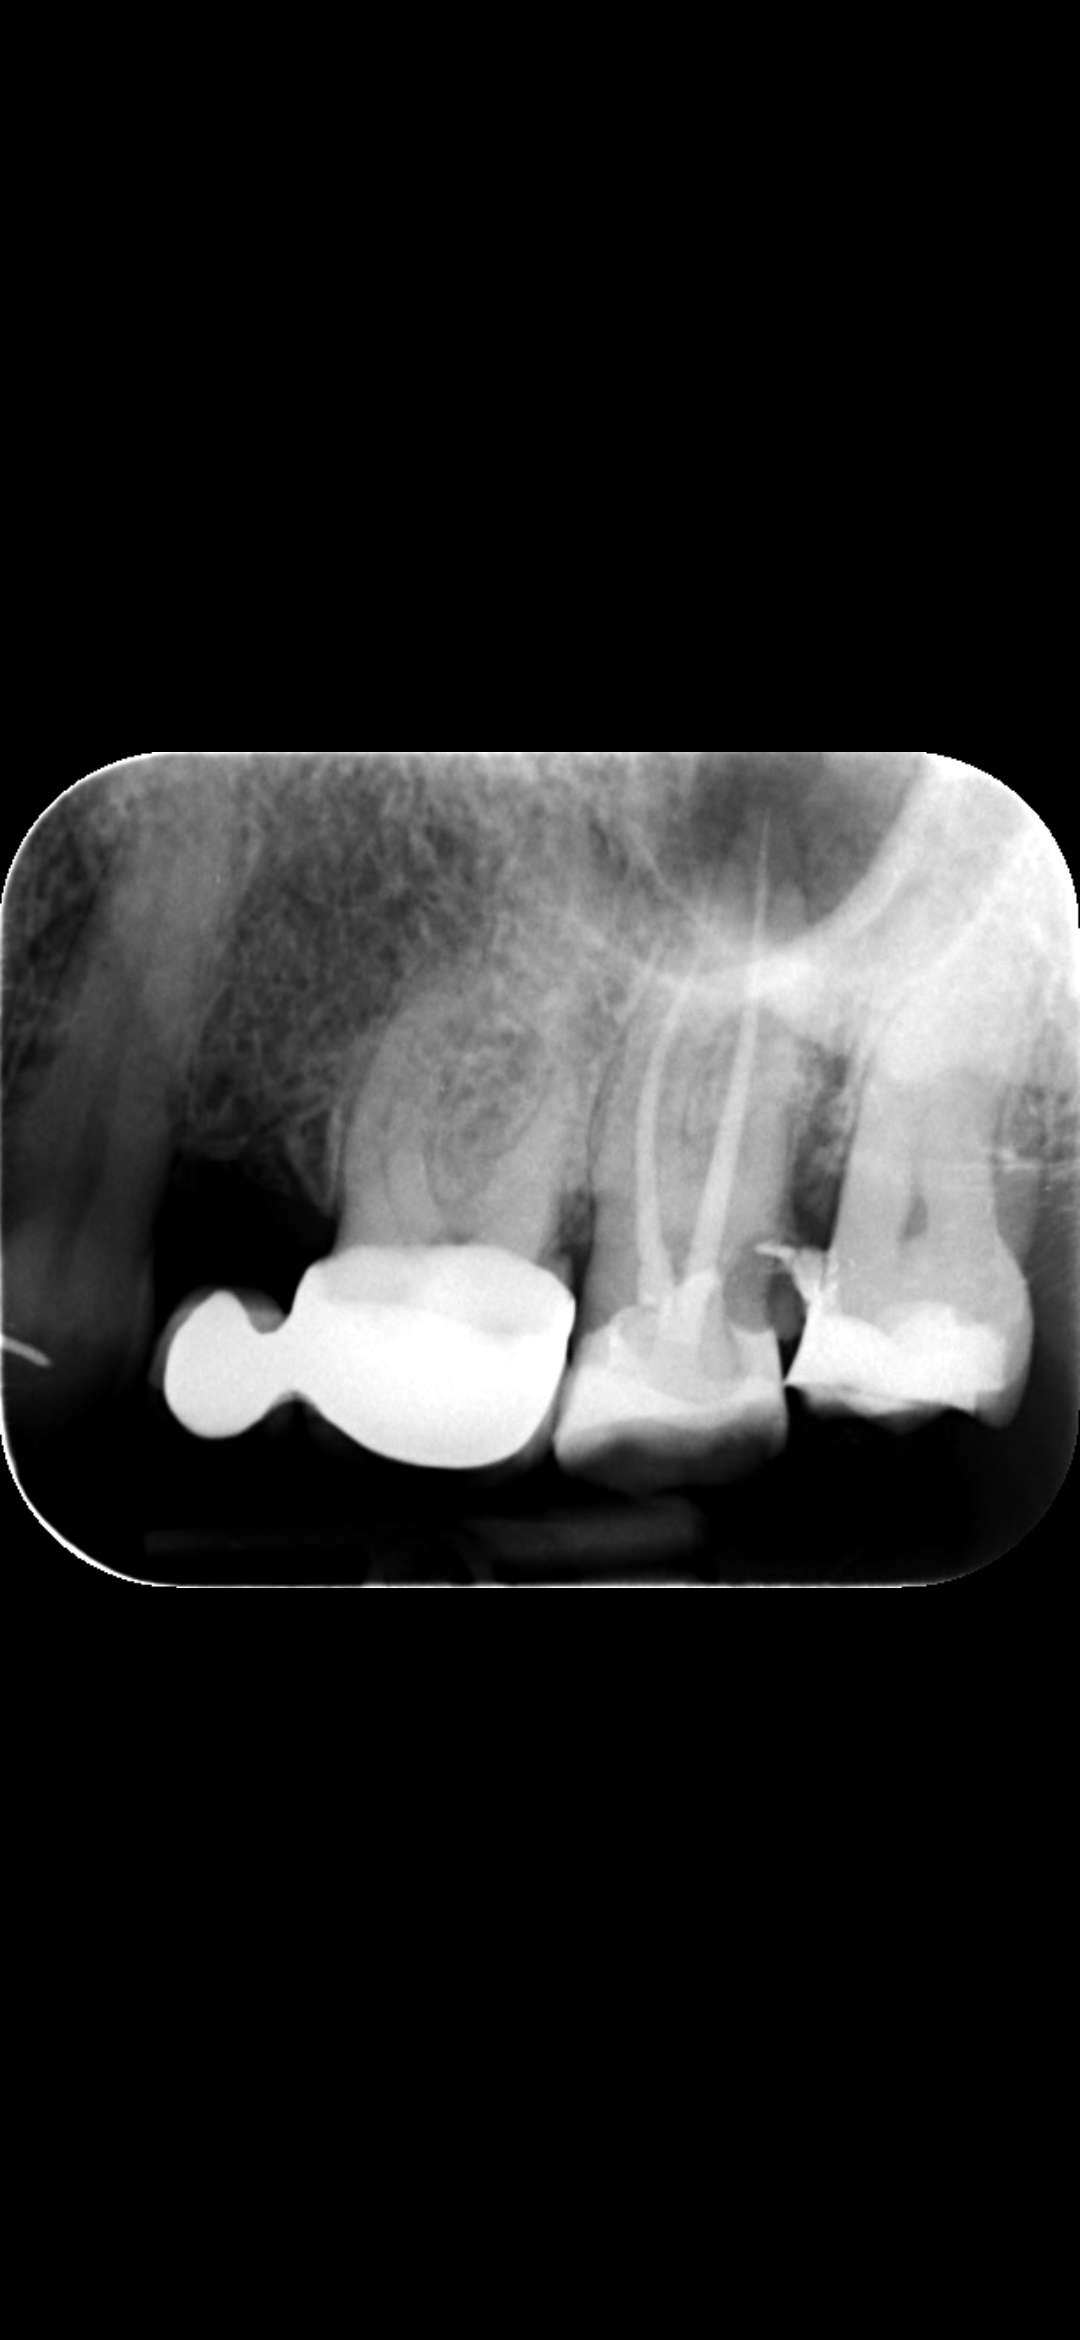

Ik ben in november naar de tandarts gegaan met een pijn in mijn bovenste kies. Voor de ene laatste. De tandarts heeft er een foto genomen natuurlijk en besloten we samen dat ze niet gaat uittrekken maar wortelkanaalbehandelen. Deze is gebeurd voor het kerst zat definief gevuld. Na een week of twee misschien begon die tand pijn doen ,gevoelig zijn en onstoken. Terug naar de tandarts. Ze heeft een foto gemaakt en tot op mijn verbazing de pijn kwam niet van de wortelkanaalbehandeld tand maar vanuit de laatste kies. Ze zei dat er een heel diep gat er in zat en moest per direct uit. Vullen was geen optie. Ik wilde met haar verder niet in discussie dus liet ik haar werk doen. Nadat ze de tand eruit rukte zei ze dat ze de wortekanaalbehandelde tand ging boren en vullen!? Toen snapte ik er niets meer van en was ook slap van de verdoving. Nu heb ik net gevoeld dat de wortelkanaalbehandelde tand is maar de helft geworden waarvan nu het helft is echt gewoon vulling materiaal die ook bijna los komt. Ik moet terug in februar dan zal ze defenitief vullen. Alleen vullen kan niet meer want deze tand heeft geen gat meer. Bijgevoegde foto is diege die genomen werd net voordat mij tand eruit moest. Kan u zien of dat echt een heel diep gat zat? Bedankt alvast

Deze is de foto van de diepe gat tussen de kiezn in. Daar moest ook mij laatste kies direct eruit. En de wortelkanaal behandeld moest nog een keer gedaan worden

WK behandelde kies moet waarschijnlijk nog een derde kanaal gevuld worden,En de achterkant is waarschijnlijk gevuld..."gaatje".

Is dat kleine zwaart puntje midden op de kies is geen gat? Wat is dat dan?

Vervolgens de arts heeft bovestaande foto gemaakt en zei dat de pijn vanuit de laatste kies kwam. En ze dat niet meer vullen kan omdat de gat zo diep is.

Daarom vraag ik mij af ..waar is de diepe gat ..kan u dat zien?